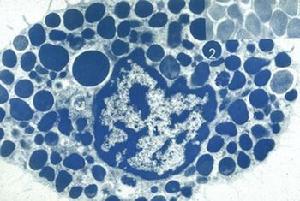

肥大細胞:細胞呈圓形或卵圓形,細胞核小,呈圓形或橢圓形,染色淺,位於細胞中央。細胞常成堆或單個分布於血管附近。細胞呈圓形或卵圓形,細胞質中充滿大小一致、染成藍紫色的顆粒,均勻分布在核周圍。

患者一般有貧血、血小板減少;白細胞總數(10—15)x109/L,肥大細胞占5%~90%。骨髓活檢示肥大細胞明顯增多,有時可達90%(26.2%—91.8%),白血病性肥大細胞呈圓形或類圓形,染色質較細緻,核仁清或不清,胞漿藍色、充滿或多或少的深紫紅色顆粒並復蓋於核上,並易見偽足和吞噬紅細胞現象。MCL的肥大細胞超微結構:核1個或多個,偶見明顯核仁。細胞漿中含有線粒體、脂質體,顆粒內容物缺乏或顆粒中充滿小粒子及典型的捲軸樣特徵。A顆粒可見,嗜鹼粒細胞的0粒不見。

(3)出現數量不等的異常形態的肥大細胞,常>20%,成堆分布,有幼稚型、成熟型及破碎型。胞體大小多在18~20nm之間,但30~40nm者亦可見到,多呈圓形、橢圓形、少數不規則形、鈍棱形及魚鉤狀,胞膜呈撕裂狀者較易見到。胞質呈淡粉或淡藍色,內有多數暗紫紅色、較粗大的嗜鹼性顆粒,可見吞噬紅細胞、白細胞現象。胞核相對較小,呈圓形、橢圓形、啞鈴狀,雙核乃至三核、分葉狀核均可見到,染色質較細,有的可見核仁。